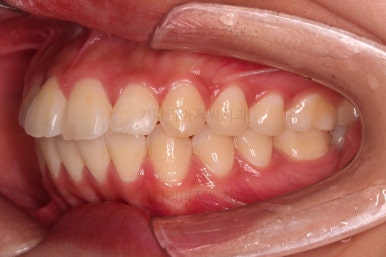

5. 마무리와 치료 종료

마무리가 잘 되었습니다.

큰 문제는 없었지만, 약간 삐뚤었던 치열이 가지런하게 정렬이 잘 되었고요.

맞물림도 매우 좋고, 뻗친 앞니 각도도 매우 좋아졌습니다.

입 안의 모습만 보면 최상급의 마무리가 되었고요.

6. 전후 사진 비교

입매가 매우 좋아졌습니다.

과연 11개월의 치료결과가 맞나 싶을 정도로 깜짝 놀랄만큼 만족스러운 치료결과였는데요.

환자분은 모르겠지만, 특정 한 포인트만 개선되면 매우 좋아질 수 있다는 중요 포인트가 있었는데 그 부분이 완벽해졌습니다.

그래서 입이 실제로 발치교정만큼 많이 들어가지는 않았는데, 그 포인트 위주로 치료를 하니 결과물이 굉장히 좋아졌던거죠.(그 포인트가 뭔지는 영업비밀입니다😀)